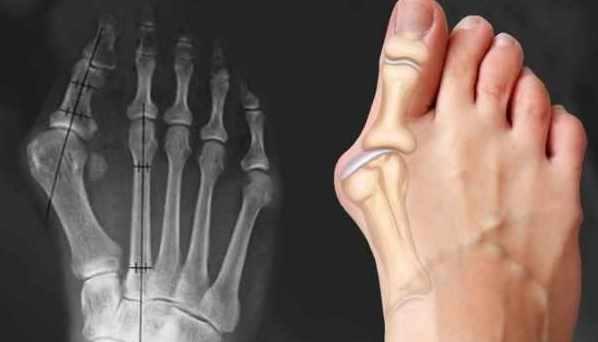

-Диагностика образований под кожей, в толще мышц, противопоказания в массаже для таких пациентов (Епифанов А.В.)